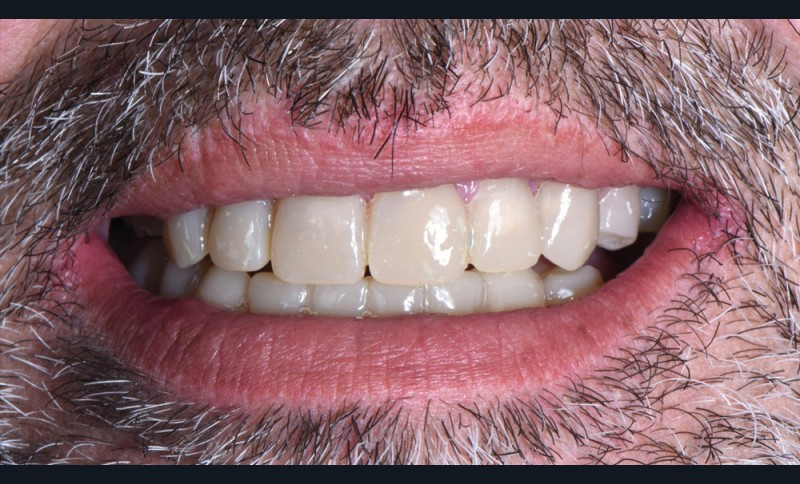

Au vu du contexte para-fonctionnel et de l’étendue de la perte tissulaire, des coiffes périphériques minimalement invasives ont été choisies afin de restaurer l’esthétique et la fonction. Actuellement, aucun consensus n’est fait sur le choix du matériau d’infrastructure à privilégier. Les matériaux hybrides usinables présentent des propriétés mécaniques, physiques et biologiques intéressantes en contexte d’usure sévère (e.g., module d’élasticité, résistance à la propagation de fêlures, facilité de réintervention). Une réhabilitation globale avec remontée de dimension verticale d’occlusion (DVO) par l’intermédiaire de coiffes composites renforcés en nano-céramiques est décrite.